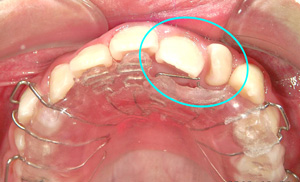

実際に装置の装着

コラム「実際に装置の装着」の画像